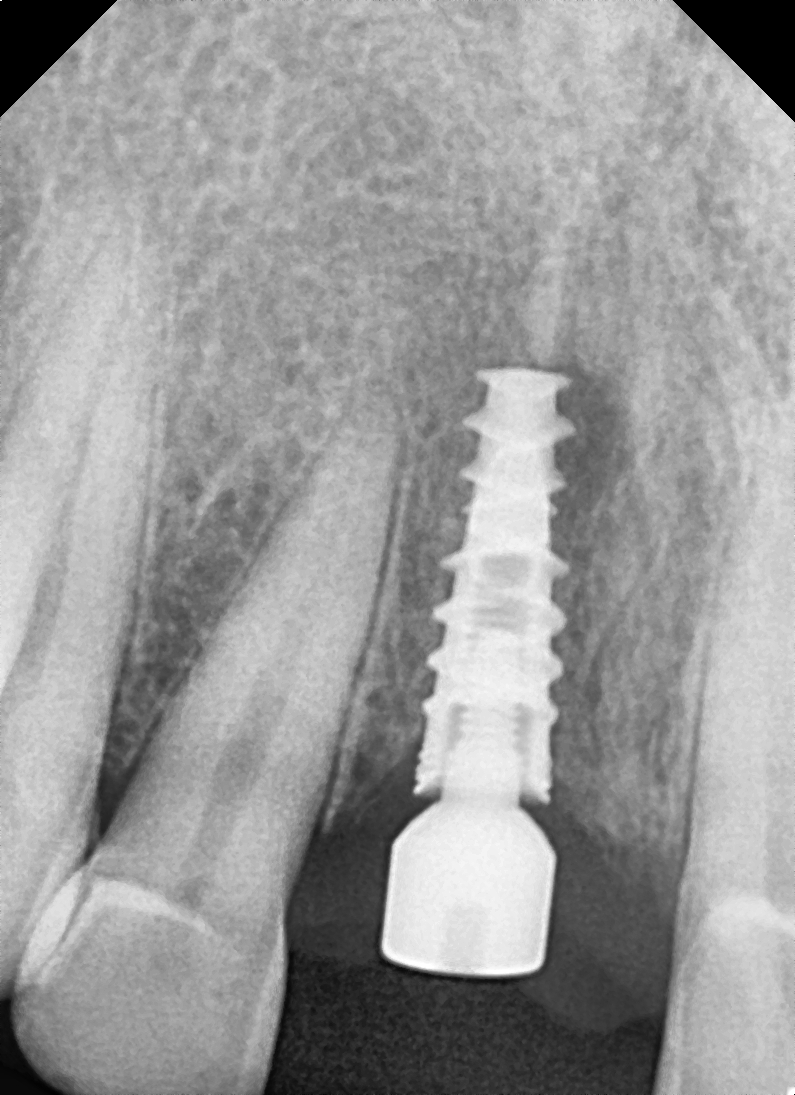

Images Of Dental Treatment Servcies Done At Our Hospital